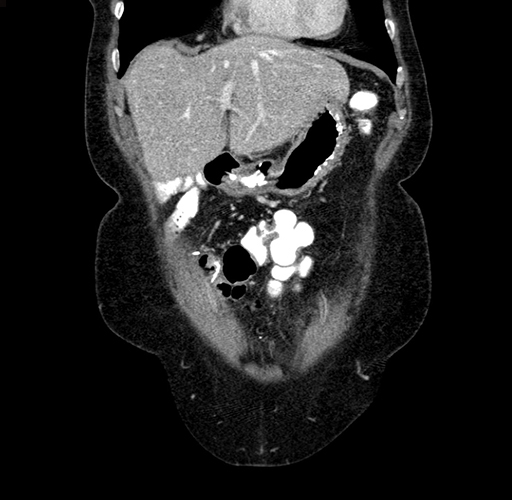

Pre-Chemo: Axial Venous

Axial Venous